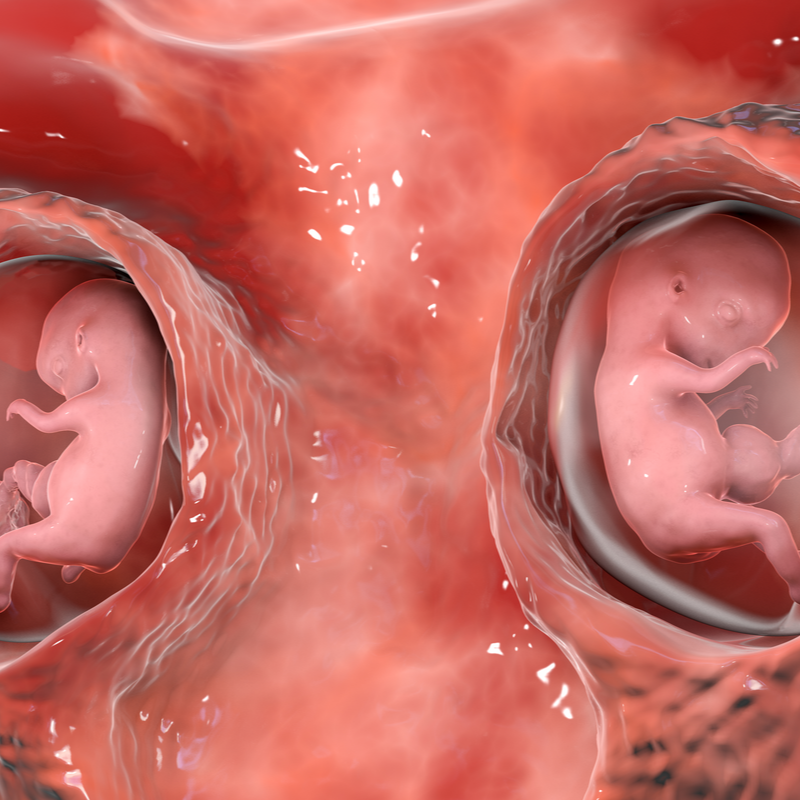

- Gynaecology and frequencies

Chorioangioma